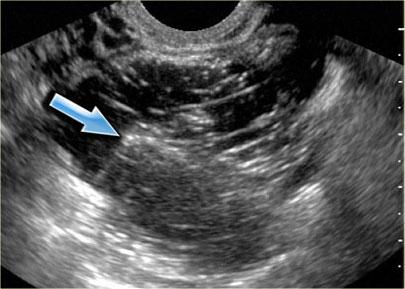

Siêu âm đường âm đạo cho thấy tổn thương dạng nang giảm âm kích thước lớn với các echo mức độ thấp lan tỏa

Trên siêu âm, hình ảnh endometrioma có thể đa dạng, nhưng đại đa số (khoảng 95%) bệnh nhân biểu hiện hình ảnh điển hình là nang đồng nhất, giảm âm với các echo mức độ thấp lan tỏa.

Hiếm gặp hơn, tổn thương có thể không có echo, dễ nhầm lẫn với nang buồng trứng chức năng.

Endometrioma có thể có nhiều ngăn và có các vách ngăn mỏng hoặc thậm chí dày.